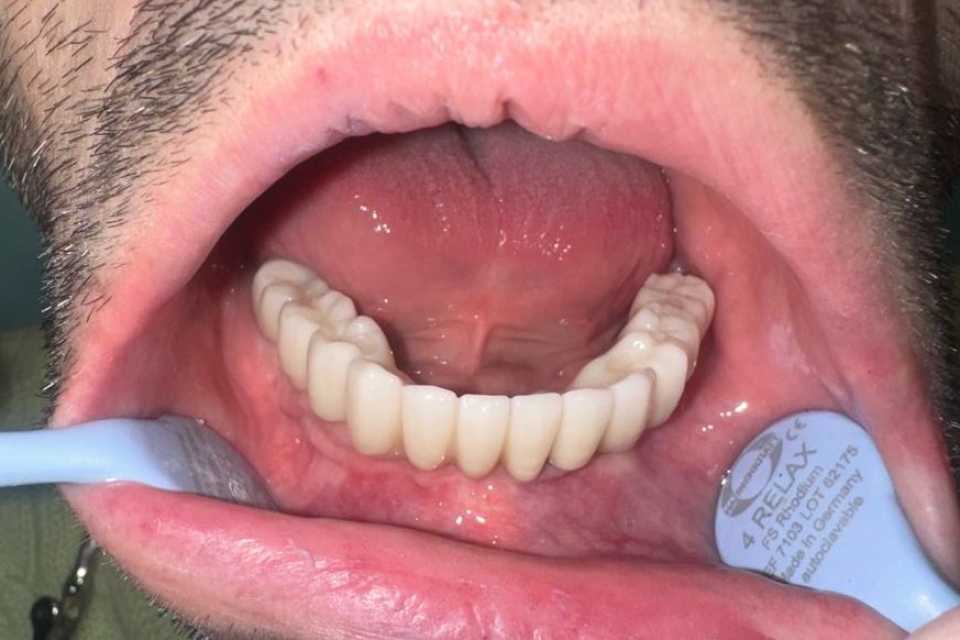

Pacientul în vârstă de 55 de ani, s-a prezentat în cabinet cu o lucrare dentara metalo ceramica ,la nivelul mandibulei, de 9 elemente pe 4 dinti parodontotici irecuperabil.

Împreună cu pacientul am hotărât inserarea a 5 implanturi dentare Mega Gen Anyridge, cu ajutorul cărora într-o prima fază am protezat a doua a zi cu o lucrare provizorie, astfel încât la 2 luni de la intervenție să realizăm lucrarea finală de 12 elemente ceramica pe zirconiu.